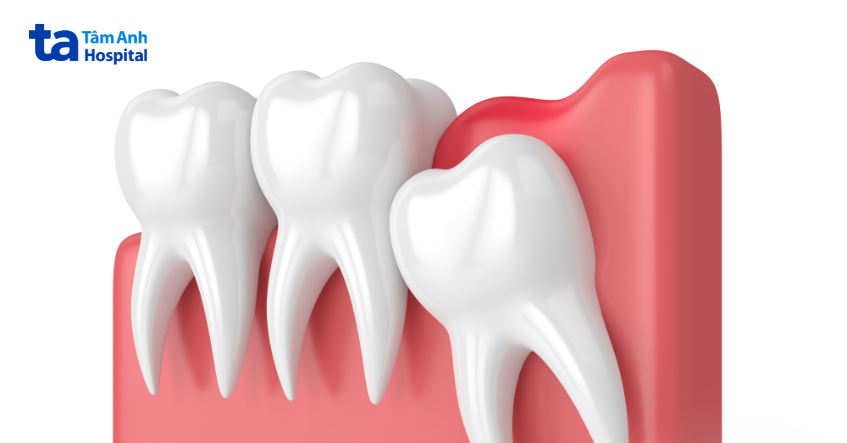

Lợi trùm răng khôn là tình trạng răng khôn bị che lấp 1 phần hoặc toàn phần bởi lợi (nướu). Lợi trùm là phần lợi bao phủ 1 phần hoặc toàn bộ bề mặt răng và ngăn cản răng phát triển. Theo thời gian, khi răng mọc lên, sẽ hình thành các khoảng trống dưới lợi, nếu không được chăm sóc và vệ sinh cẩn thận sẽ là nguyên nhân dẫn đến các bệnh về lợi như viêm lợi, viêm nha chu, viêm lợi trùm,…

Lợi trùm sẽ ngăn chặn sự phát triển bình thường của răng khôn. Phần mô mềm bao phủ trên răng khôn, hay còn gọi là túi nướu sẽ tạo điều kiện cho vi khuẩn sinh sống và phát triển, gây nhiễm trùng cục bộ và sưng tấy vùng nướu tại chỗ, sau đó có thể lan sang các răng lân cận. Từ đó, mô nướu bị viêm hoặc sưng sẽ bao phủ bề mặt răng.

Răng khôn là chiếc răng mọc cuối cùng trong hàm răng, vì vậy chúng thường thiếu chỗ trống để mọc lên hoàn toàn theo đúng hướng. Răng khôn vì vậy dễ mọc theo nhiều tư thế khác nhau như mọc ngầm, mọc nghiêng, mọc ngang,… Hướng mọc của răng không đúng làm cho lợi dễ bị sưng lên, viêm nhiễm và trùm lên răng khôn và khó làm sạch khi vệ sinh răng miệng, điều này tạo điều kiện cho vi khuẩn sinh sôi và phát triển.